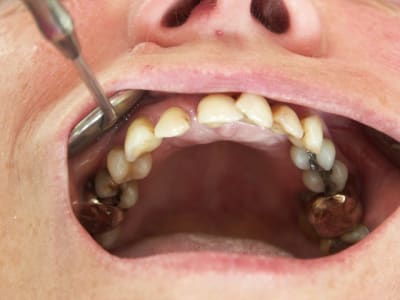

2010 bridge provisoire sur ANKYLOS, extaction, mise en charge immédiate bridge provisoire à armature métal sans scellement en 1 seul temps chiurgical.

Chirurgie à PAMIERS, préparation prothétique et dispositif de forage à MONTASTRUC LA CONSEILLERE, dans notre belle campagne de France.